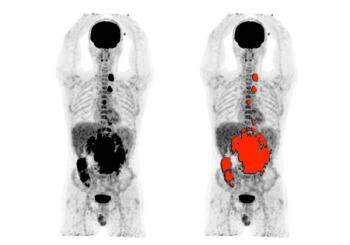

Measurements can help predict which tumors will respond to targeted therapies.